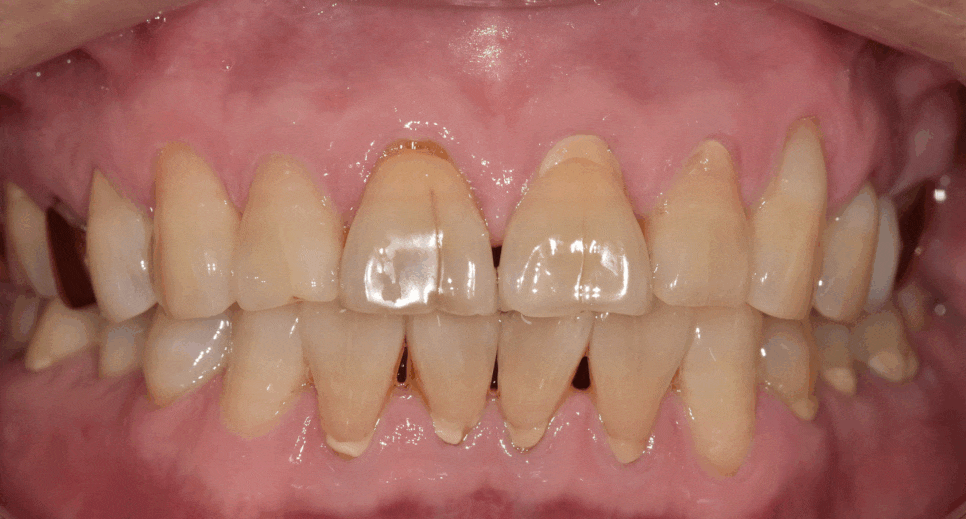

앞니 통증이 갑자기 심해져 내원하신 환자분의 사례입니다.

치아를 살펴보니 앞니 앞면 중앙에 금이 쭉 가 있었습니다.

치경부(치아와 잇몸 경계) 쪽엔 마모가 진행되어 뿌리 쪽이 파여있습니다.

250626 앞니 금 갔을 때, 방치하면 안 되는 진짜 이유 <파절 치료 사례>

특히 금이 더 깊게 간 오른쪽 앞니 통증을 호소하셨습니다.